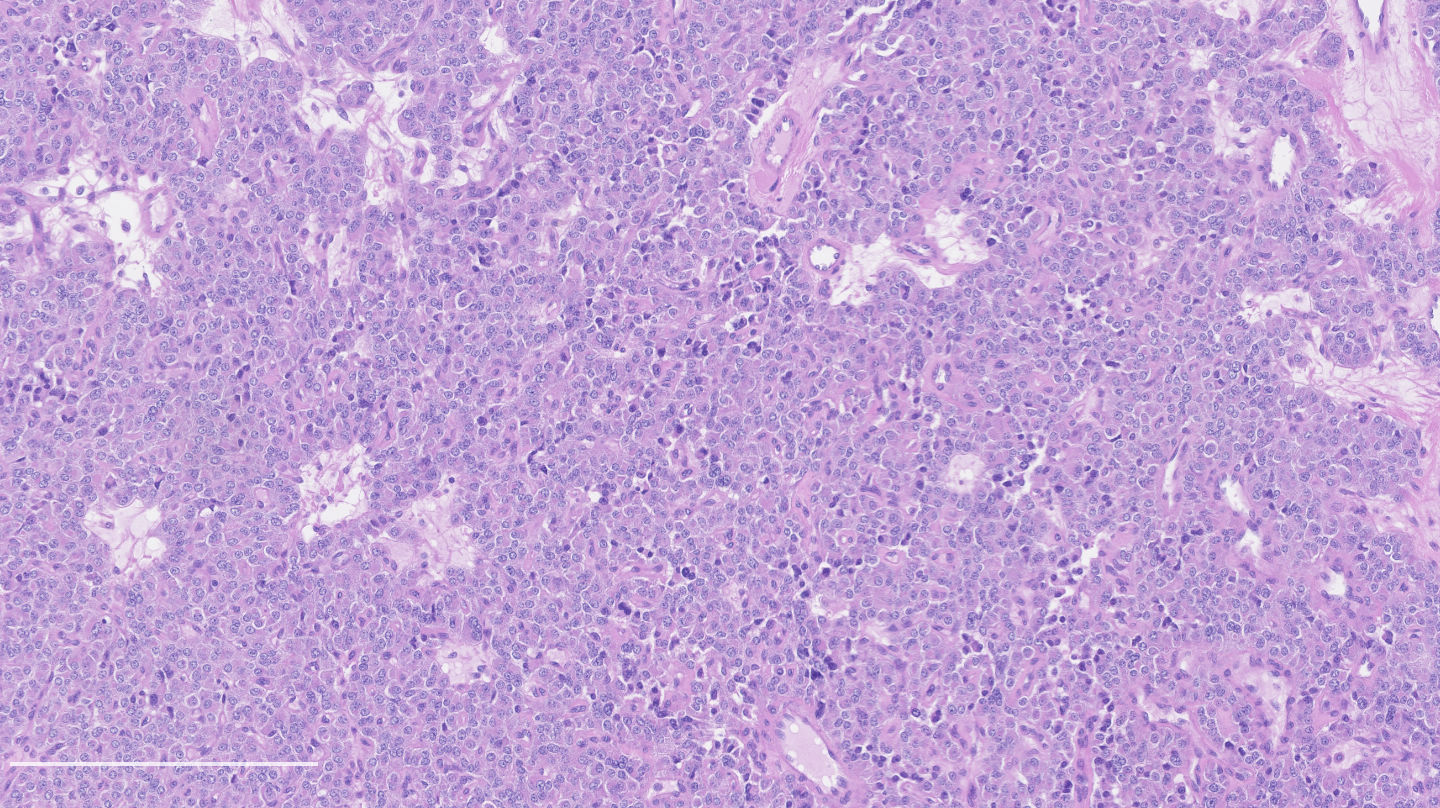

- Neuroendocrine histologic patterns similar to typical carcinoids: organoid, trabecular, rosette formation, papillary, pseudoglandular, follicular

- Tumor cells are as typical carcinoid: uniform with a polygonal shape, round to oval nuclei with salt and pepper chromatin and inconspicuous nucleoli, along with moderate to abundant eosinophilic cytoplasm

- Greater pleomorphism than for typical carcinoid is common (Arch Pathol Lab Med 2010;134:1628)

- Spindle cells and clear cell features can be seen

- Stroma is fine and highly vascularized; hyalinization, cartilage or bone formation are possible

Contributed by Philippe Joubert, M.D., Ph.D.